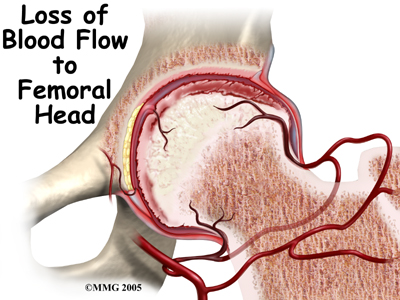

Whatever the true cause of ischemia (lack of blood to the area), the result is bone death (called necrosis) of the femoral head. Without a normal blood supply, the bone loses its strength and shape. The loss of bone density and softening of the head result in a femoral head that is misshaped. With the hip supporting the weight of the body, tiny microfractures in the soft, necrotic bone fail to heal. This is another reason why normal wear and tear results in a deformity.

The main problem with Perthes disease is that it changes the structure of the hip joint. How much it affects the way the hip joint works depends on how much the hip joint is deformed. Muscle weakness and atrophy affecting the thigh and calf muscles may develop over time. The affected leg can shorten as a result of the changes in the hip. The result may be a significant leg length difference. Problems later in life are more likely the greater the deformity after the condition has healed.

The main problem with Perthes disease is that it changes the structure of the hip joint. How much it affects the way the hip joint works depends on how much the hip joint is deformed. Muscle weakness and atrophy affecting the thigh and calf muscles may develop over time. The affected leg can shorten as a result of the changes in the hip. The result may be a significant leg length difference. Problems later in life are more likely the greater the deformity after the condition has healed.

In general, the most common problem later in life is the development of arthritis in the hip joint. The type of arthritis that develops in the hip is osteoarthritis (also known as wear and tear arthritis). Just like a machine that is out of balance, the hip joint wears out and becomes painful.